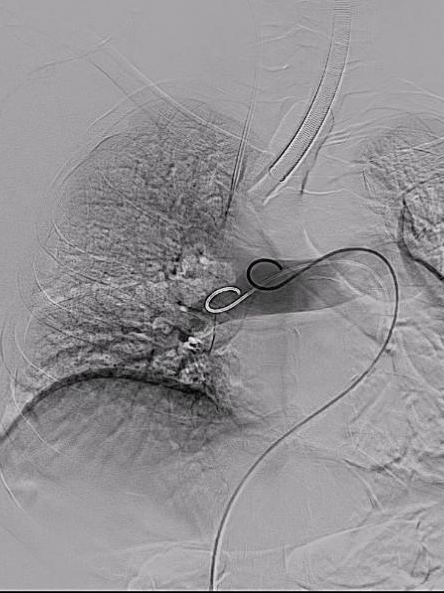

手术过程:

血管外科团队顺利完成股静脉穿刺,置管造影,然后在DSA指引下顺利送入抽吸导管至左右肺动脉主干,以取栓系统取出大量新鲜、陈旧混杂血栓,双肺末梢动脉即刻恢复灌注。

右肺取栓前后影像